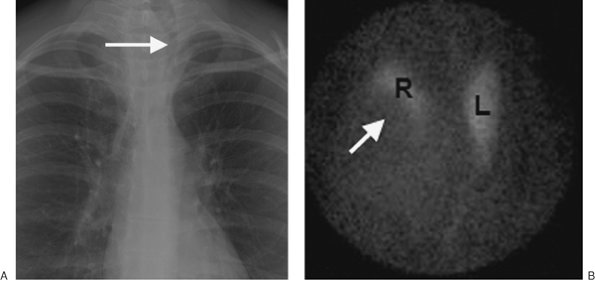

Aortic dissections are collections of blood within the media of the aortic wall that communicate with the true aortic lumen through one or more tears in the intima. Most dissections begin within an intimal tear, and bleeding splits the aortic media. Two classification systems are used to describe aortic dissection. The DeBakey classification divides aortic dissection into three types (15). Type I refers to dissections that start in the ascending aorta and extend into the descending aorta; type II, to dissections confined to the ascending aorta; and type III, to dissections that start just beyond the left subclavian artery and are confined to the descending aorta. The Stanford classification refers to type A (involving the ascending aorta) and type B (confined to the descending aorta) (16). The diagnostic feature of aortic dissection on contrast-enhanced CT scanning is two lumina separated by an intimal flap (Fig. 6-28). The intimal flap is seen as a curvilinear low-attenuation area within the opacified aorta. A false lumen usually fills and empties in a delayed fashion compared with a true lumen. The false lumen may be partially or totally filled by thrombus and therefore may not opacify. The true lumen is usually compressed by the false lumen. Displacement of calcified atheromatous plaques by the dissection can be demonstrated on precontrast CT scans when contrast enhancement of the two lumina cannot be achieved (as with a thrombosed false lumen). Aortic dissection is further discussed along with other aortic pathology in Chapter 19.